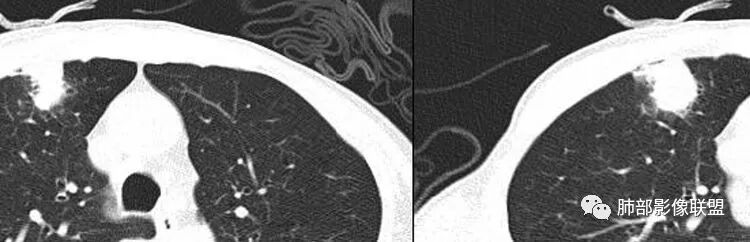

南边:周围晕、细微毛刺都属于炎性特点这一部分单独拿出来类圆形,边缘光滑,按理恶性特征不明显;但是加在一起,转移瘤就不排除总体倾向于炎性,转移瘤不除外

南边:就目前的征象符合炎性,我认为炎性病变一定有但是有部分边缘膨隆,恶性不能排除,等炎性吸收后看看,或穿刺血管纠集南边:

南边:我们担心的,它是在一个转移的基础上,还有合并有炎症,担心这个隐藏在其中,因为它这个边缘,是不是很清楚光滑哈,但是我们都记得转移瘤,他很多都是边界清楚光滑的,对不对。就觉得,中间这个结节跟周围的病灶好像形态、密度各方面都不一致的。我就担心它是一个转移瘤,合并感染,周围炎性病变,中间是一个转移瘤结节这样的就麻烦了。所以常规我会建议他抗炎治疗后复查。看看那个残留的病灶怎么样,本质是如何,要么穿刺,这个病变我只能说炎性它一定有。南边:里面那个病灶就是那个类圆形的病灶,跟外面那个肯定是不一致的,就那个类圆形病灶,到底是一个转移瘤,还是单纯炎性病变的部分。目前这个片只能等复查,毕竟边缘是膨隆的,而且我们刚才也说了,转移瘤的特点,如果血道转移,他就是边界清晰光滑的。所以成这样,有这么巧的话你就没办法。南边:关于血管纠集,它就这样的,炎性病变也可以这样表现,牵拉过来,原理不同,但是影像表现已经表现很类似,我们往往关注支气管。支气管进入这个病灶的表面的时候是否堵塞,或者血管,进入这个病灶里面,是否走行是否自然;这些这些可能价值大一些,但是他是不是一个恶性征象,是;但是它的比例就是在炎性病变也不低。原发呢,不敢说没有,但是一般来说几率偏低吧。

结果:活检病理:右上肺肺泡慢性炎;肺泡腔内纤维素样渗出伴出血。

1.胸膜下不规则结节影,密度不甚均匀,有浅分叶、长毛刺,周边有磨玻璃晕。

2.有胸膜牵拉,尽管收缩能力不强。支气管相关(有细小支气管止于病灶内侧),加之病灶孤立、边界不清带晕,这些都不是血道转移病灶的特点。

综上,更支持慢性炎性病灶。隐球菌感染不能排除,无论是影像特点,还是患者不相关的临床表现。